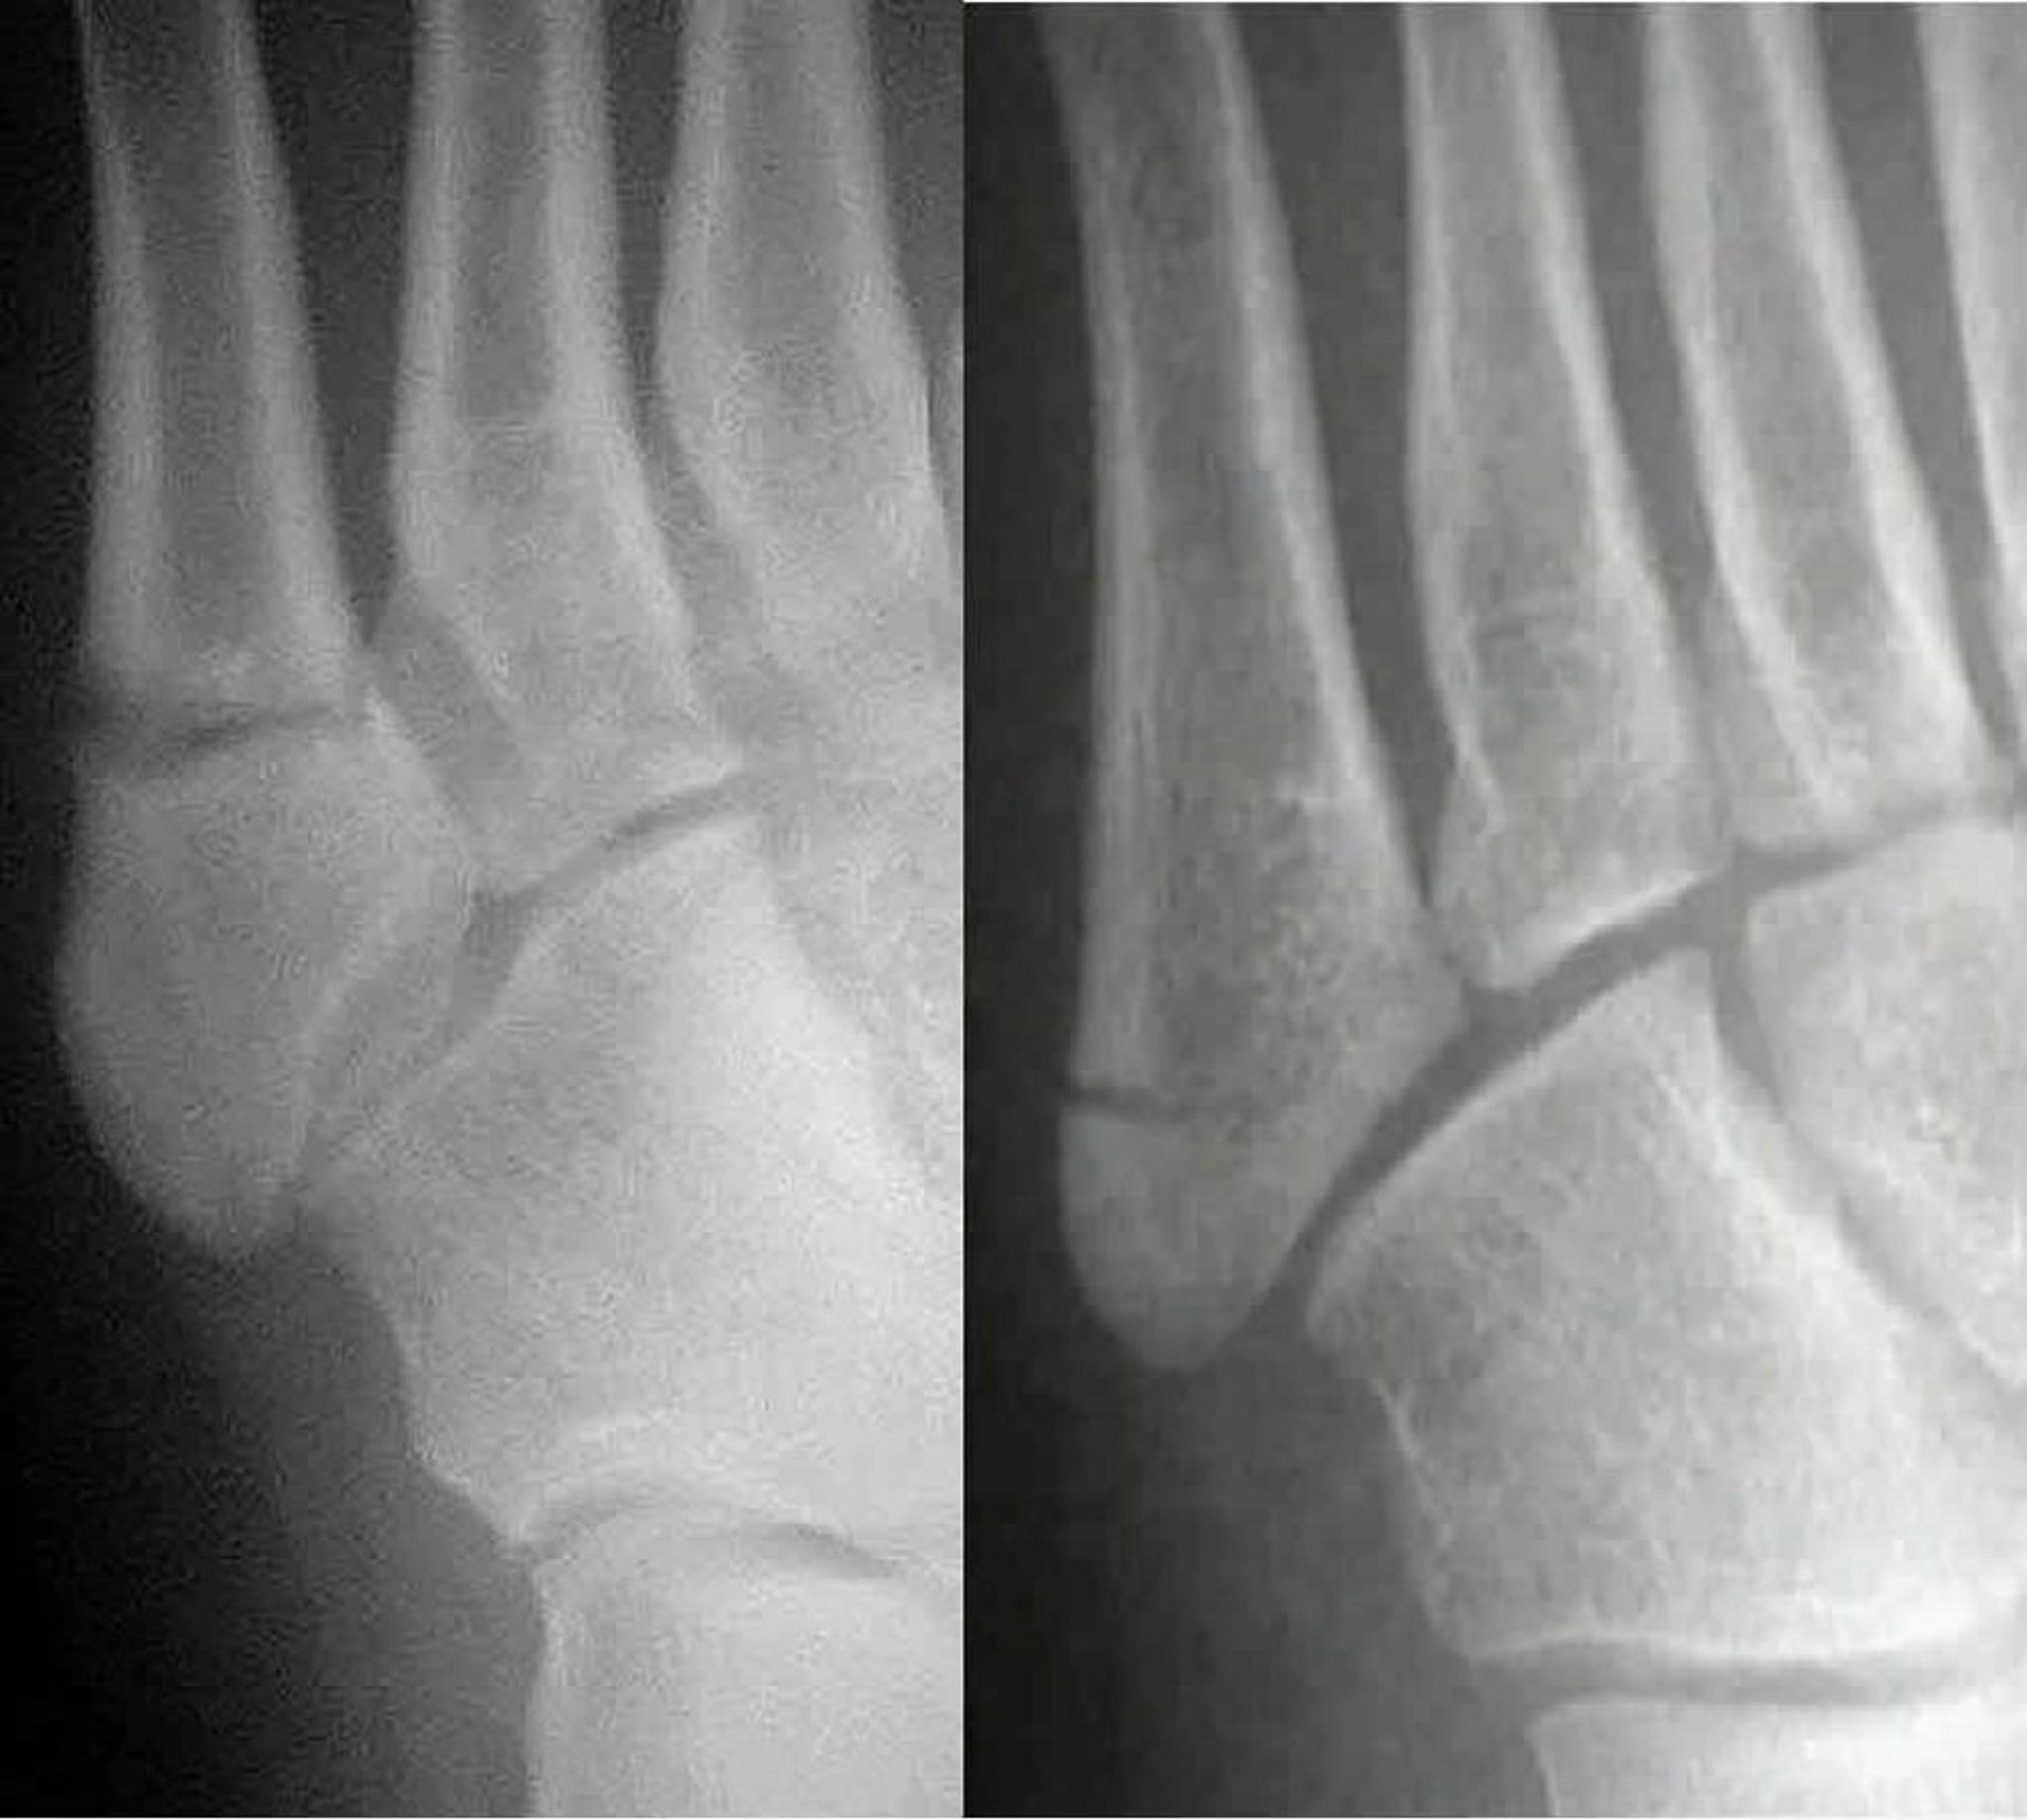

Fraturas de Jones versus pseudo-Jones

A fratura de Jones (à esquerda) compromete o 5º eixo metatarsal; a pseudo-fratura Jones (à direita) envolve a 5ª base metatarsal. É importante diferenciar as duas porque são tratadas de forma diferente.